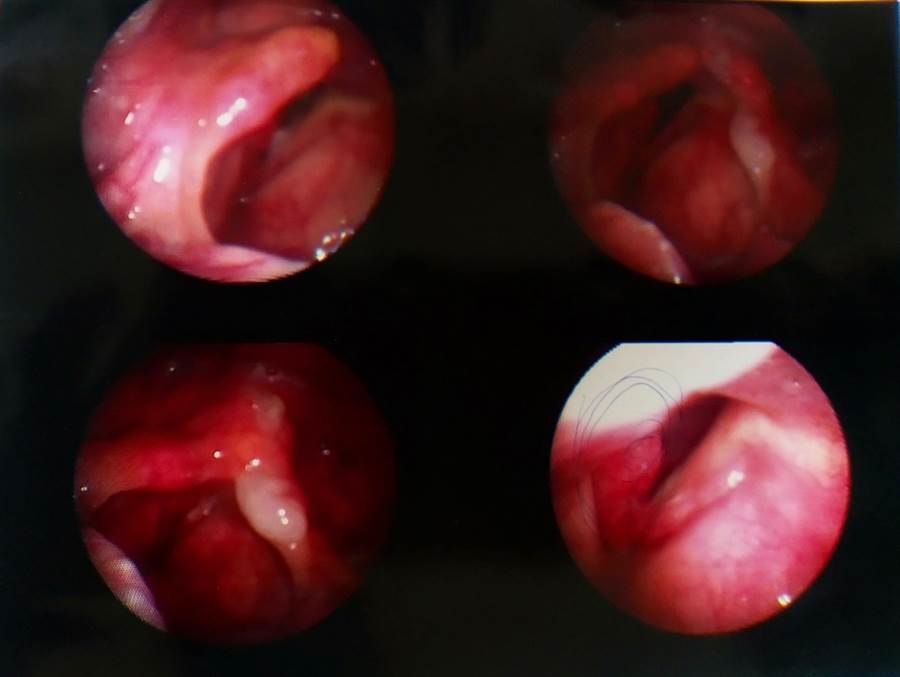

咽喉癌的早期症状图 好医师网 好医生在线 24小时免费咨询 帮您免费快速

咽喉炎图片和正常图片 自己排除喉癌的方法 帮助信息 动天数据